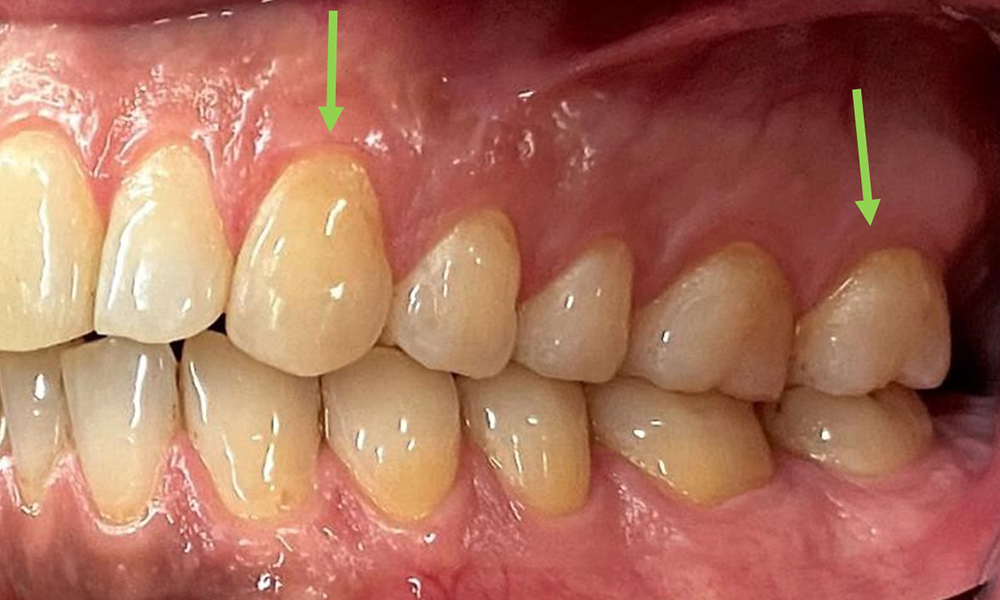

Instruktion & Motivation sind wichtige Bestandteile in der Sitzung. Gutes

häusliches Mundhygieneverhalten und – verständnis sind dem Patienten wichtig. Es zeigen sich insbesondere an den ZahnhalsbereichenPlaqueakkumulationen (Abb. 8).

Plaqueakkumulationen im Zervikalbereich

Abb. 8: Die Pfeile markieren Plaqueakkumulationen im Zervikalbereich, © Dr. R. Krapf

Diese sind mit dem Patienten zu besprechen und Verbesserungen in der Zahnputztechnik zu üben. Gerade aufgrund der Erosionen und Attritionen ist ein weicher Zahnbürstenaufsatz für die häusliche Mundhygiene anzuraten.